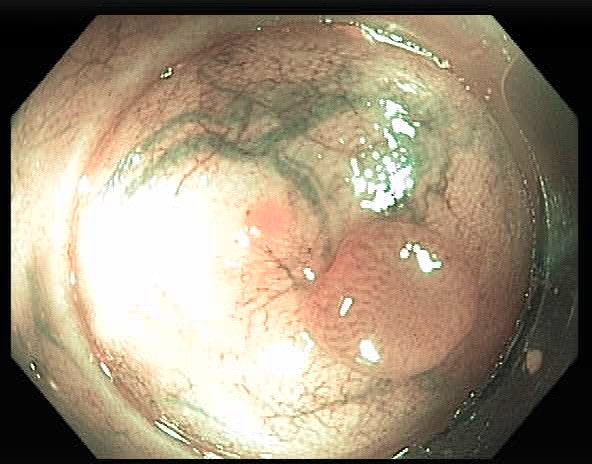

Based on the classification of each frame, we can measure the performance of each sequence. The sequence-by-sequence performance for the two datasets are shown in Fig 5 and Fig 6, respectively. We can see that the results are not consistent among all frames within the same sequence of the same polyp. This is because the appearance of the polyp may subject to significant appearance changes due to the variance of the viewpoints, zooming scales, and illumination. Fig 7 shows some sample frames of a sequence under different viewpoints and lighting conditions. In this case, even experienced endoscopists cannot make an accurate prediction from a single frame. As a result, not all frames can be correctly classified. In practice, we calculate the percentage of correctly classified frames for each sequence. Then, we set a threshold in terms of the percentage, and a sequence is considered to be correctly classified if the percentage of correctly classified frames is greater than the specified threshold. Table 5 shows the performance corresponding to different thresholds for the two datasets.

As shown in Fig 5 and Fig 6, the classification result for each sequence is not consistent. The test sequences 1, 3, 10, 12, 13, 14, 18,19, 21, and 22 are correctly classified by all models for both datasets, while the results of sequences 2, 4, 5, 6, 7, 9, 11, 17, and 20 are not consistent because the percentage of the correctly classified frames is in between 40-50%. Sequences 5 and 6 could not be classified well by all models. Some sample frames of sequences 5 and 6 are shown in Fig 8, which subject large variations in appearance that cause the difficulty in classification. Table 5 shows the threshold-based performance of all models. The results indicate the consistency of the prediction of different models, from which we can see that VGG models achieve relatively better performance than other models. For example, VGG-19 achieves around 70%, 80%, and 90% accuracy at the thresholds of 70%, 60%, and 50%, respectively. Comparing Table 3 and Table 5, we can find that if we set the threshold at 50%, the sequence-based accuracy is much higher than frame-based based accuracy, especially for VGG models. However, at a higher threshold of 70%, the overall accuracy of the frame-based is higher than the sequence-based approaches, which indicates the consistent prediction within the sequence.